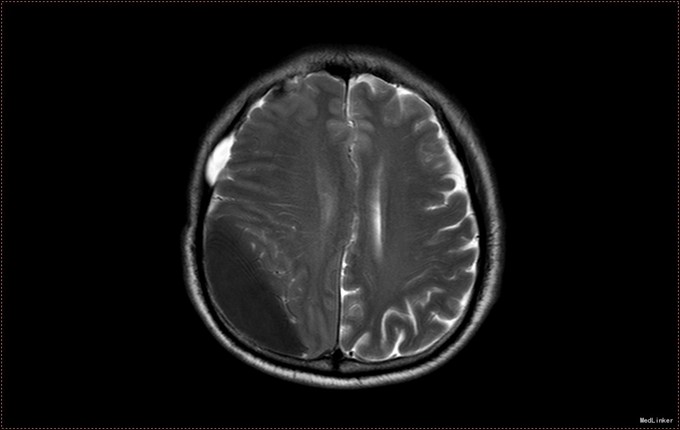

患者,男,53岁。以“左侧肢体疼痛伴无力1周”为主诉入院。患者1周前无明显诱因出现左侧肢体无力,伴酸痛,头部闷胀感,症状持续不缓解,于我院就诊,行头部CT及MR提示右侧顶枕叶硬膜下血肿。右侧额颞叶蛛网膜囊肿。患者为求进一步治疗,急诊以“硬膜下血肿”为诊断,收入病房。患者病来精神状态差,饮食睡眠可,二便可,体重无明显变化。否认近期头部外伤史。

入院查体:T:36.5℃ ,P:68次/分 ,BP:130/80mmHg , R:16次/分。步入病房,自主体位。神清语明,问答准确,查体合作,精神状态良好,定向力完整。粗测视野正常,双侧瞳孔等大正圆,D≈3.0mm,双侧眼球活动自如,对光反射灵敏。四肢活动自如,左侧肢体肌力V-级,右侧肢体肌力Ⅴ级,肌张力正常。深浅感觉检查未见异常。头CT及MR提示右侧颞极蛛网膜囊肿,右侧亚急性硬膜下血肿

患者诊断明确,完善术前检查行局麻右侧钻孔冲洗引流术,予常规治疗。术后3天拔管,复查头CT硬膜下血肿消失,但脑组织膨胀不良。患者左侧肢体肌力恢复正常,无头晕头沉症状,顺利出院。